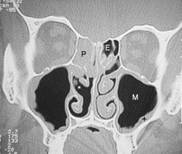

Da man sich als Laie schlecht vorstellen kann wo genau diese Nasenmuscheln in der Nase sitzen hier zusätzlich zu dem oberen Bild ein frontaler Querschnitt durch das Mittelgesicht:

Abb. 1   Abb. 2

Abb. 1: Hier relativ normale Verhältnisse. Die Nasenmuscheln lassen noch genügend Luft (schwarz) durch die Nasenhöhle strömen obwohl die Scheidewand leicht verkrümmt ist. Die Kennung IT zeigt wo sich die entsprechende zu verkleinernde Nasenmuschel befindet

Abb. 2: Auf der rechten Seite des Bildes sehen sie verdickte untere Nasenmuschel und seitlich daneben die Kieferhöhle (M). Die Nasenatmung ist hier einseitig stark eingeschränkt. Die dünnen schwarzen Linien stellen die noch verfügbare Nasenatmung links dar!

Erklärung: Schwarz: Luft, Graustufen: Weichteile, Weiß: Knochen, IT: untere Nasenmuschel, M: Kieferhöhle, S: Nasenscheidewand